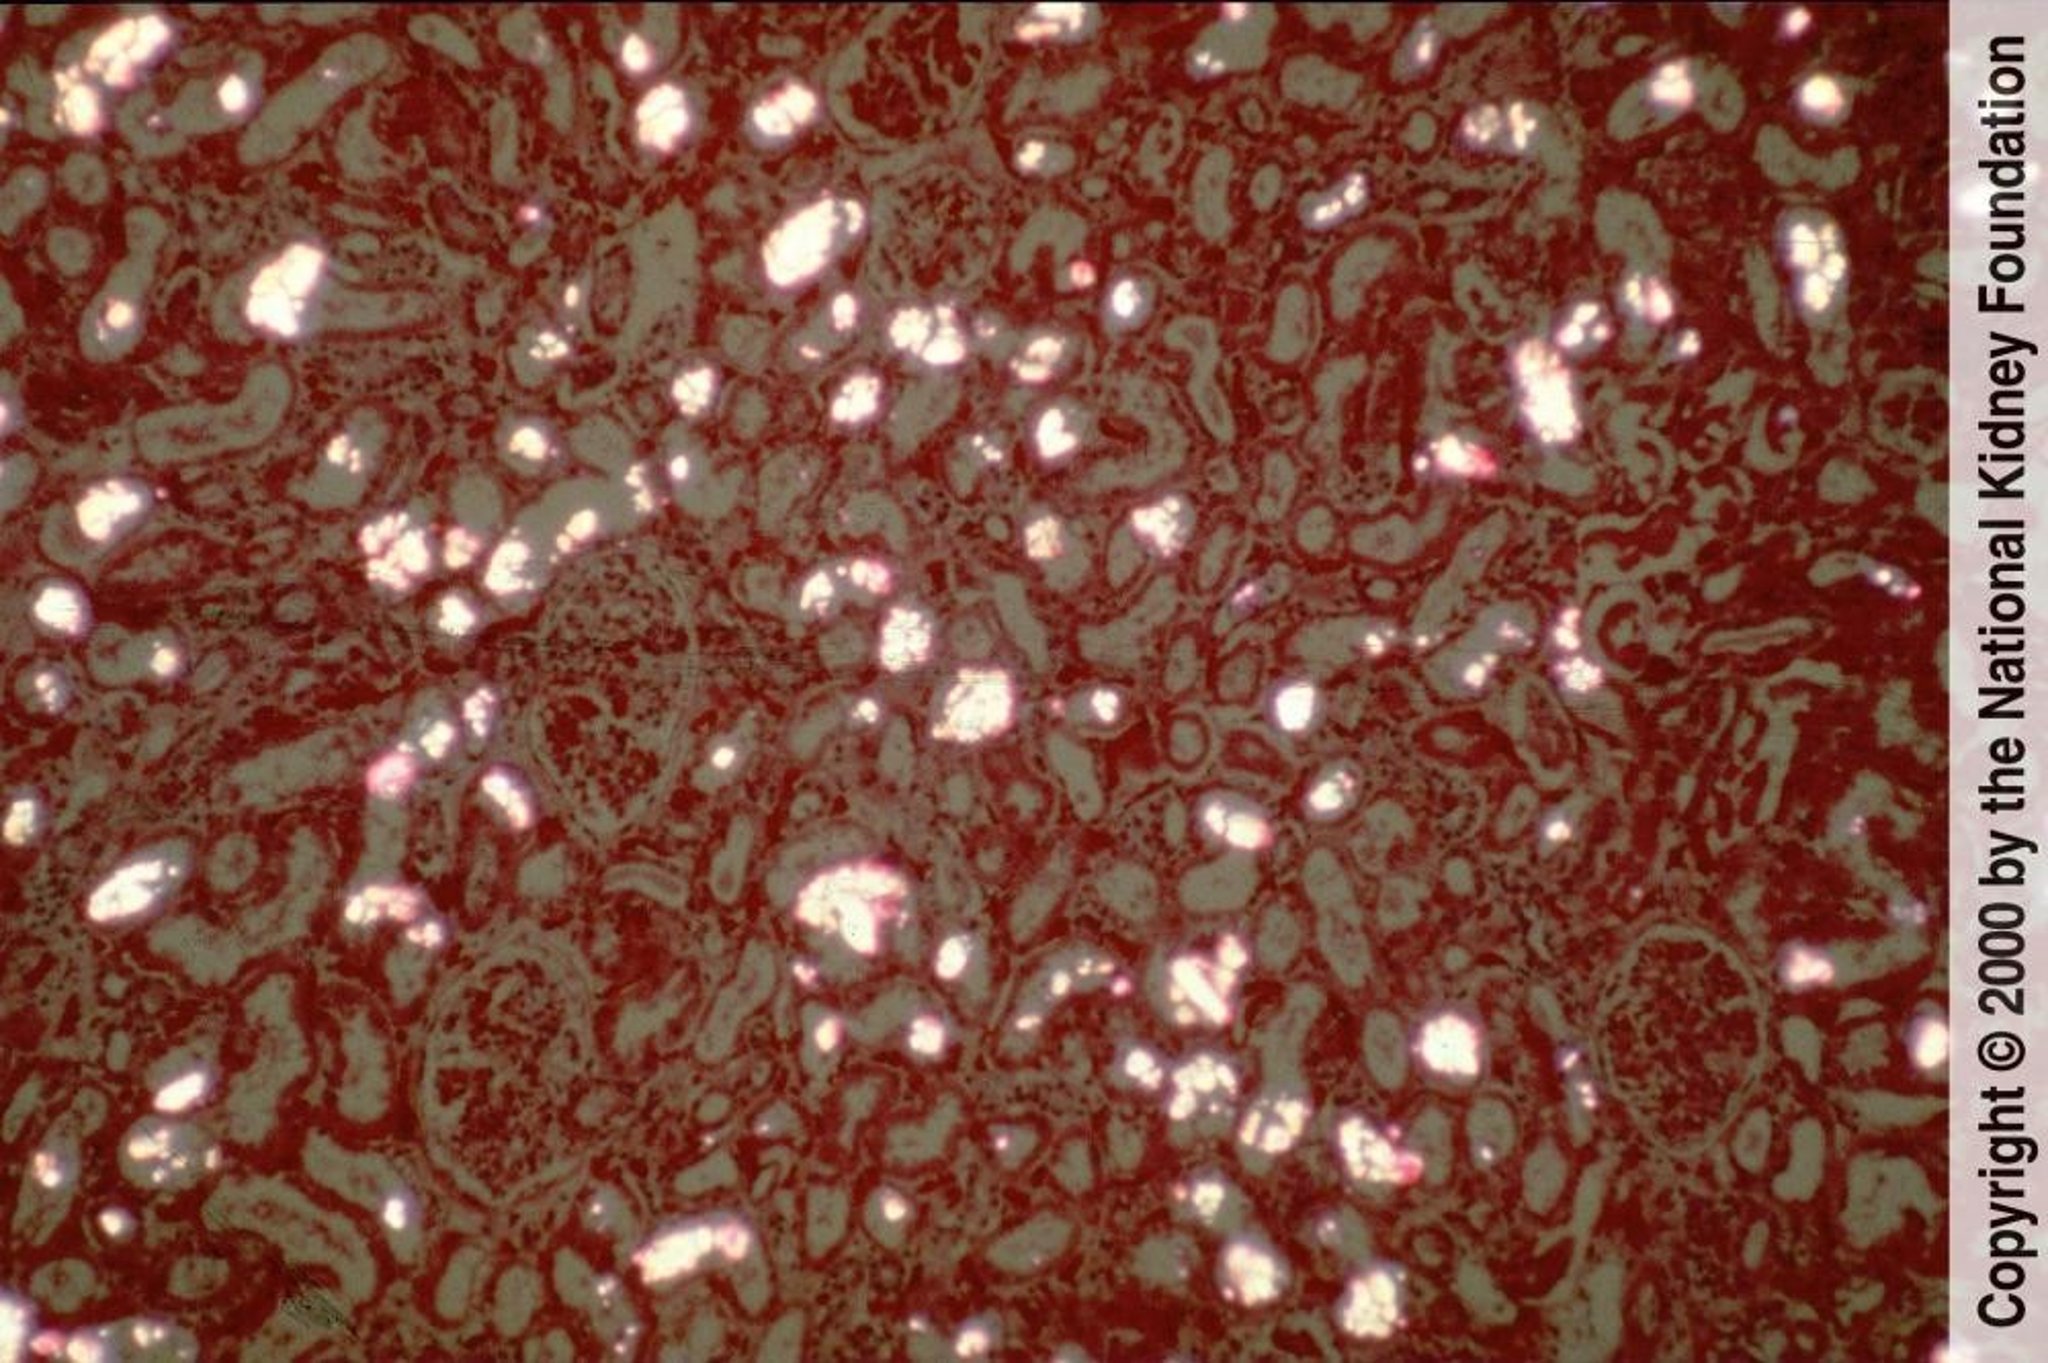

Calcium oxalate crystals precipitate in renal tubules and are easily visible as birefringent and fan- or sheaf-shaped crystals under polarized light (polarized hematoxylin-eosin stain, ×100).

Image provided by Agnes Fogo, MD, and the American Journal of Kidney Diseases' Atlas of Renal Pathology (see www.ajkd.org).